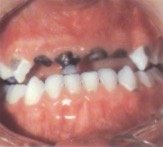

Dental Hygiene: Tooth eruption begins at 5-6 months; promote good dental care.

Baby Bottle Syndrome

Baby bottle syndrome is the decay of front teeth and molars due to prolonged bottle feeding, continuous use, or falling asleep with the bottle. Extraction of affected teeth is often required.